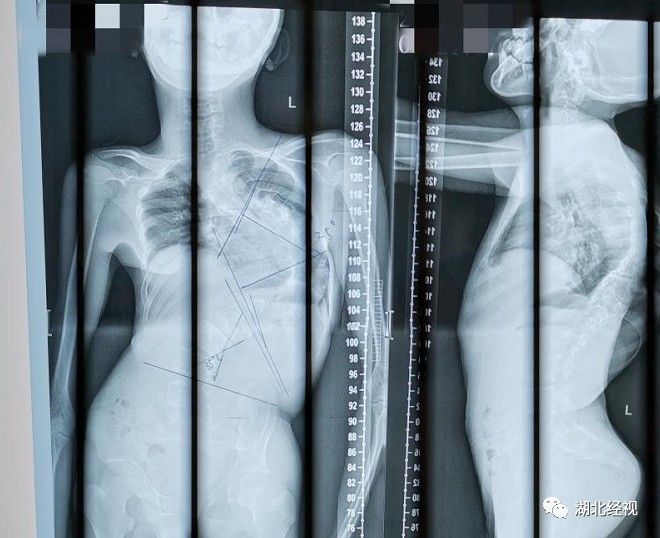

14岁少年脊柱侧弯131度湖北经视采访人员了解到,4年前,湖北黄冈李先生发现10岁的儿子不仅驼背,而且有明显的高低肩,在当地医院检查发现,竟然是特发性脊柱侧弯。由于当时小文脊柱侧弯Cobb角不足40度,还未达到手术治疗的指征,当地骨科医生建议他先保守治疗,佩戴矫正支具。

可随着小文进入青春期,骨骼生长发育加快,其背部畸形愈加明显。去年受疫情影响,小文未能及时就医对支具进行有针对性调整,当他今年再次回到医院治疗时,脊柱侧弯Cobb角已经增大至131度,属于重度脊柱侧弯。

由于背部畸形,小文头部总是不自然的倾向一侧,行走姿势也十分怪异。生理上的不适和体型上的畸变严重影响到小文的日常生活,他心生自卑,不愿主动与人交流,昔日开朗的男孩变得日渐拘谨、沉默寡言。家人看在眼里,急在心里,带小文辗转于省内各大医院就诊,但医生都因手术难度大、风险系数高,而不敢冒险。一筹莫展之际,小文一家慕名来到武汉大学人民医院脊柱外科就诊。该科主任陶海鹰教授接诊时发现,小文的背部呈明显的“S”形,更为严重的是由于脊柱侧弯程度加重,胸腔发育受限,左肺出现肺不张的情况,进一步检查显示,小文存在极重度通气功能受限。必须尽快手术矫正,否则小文将面临呼吸衰竭、心脏衰竭、瘫痪甚至死亡的危险。手术帮其“扶正”腰杆陶海鹰教授介绍,脊柱侧弯矫正手术,需要在弯曲的脊柱椎体骨两侧打上螺钉,再将螺钉连接起来,利用这套钉棒系统将椎体尽可能拉直,以此达到矫正的效果。脊柱不仅有着重要的脊髓神经组织,且毗邻心脏、肺脏、主动脉等极其重要的脏器组织,因此手术难度大、风险高,稍有不慎就可能造成截瘫,甚至危及生命,因而被誉为骨外科手术“皇冠上的明珠”,对手术医生的手术技术和团队配合程度考验极大。术前,脊柱外科、麻醉科、手术室、放射影像科等多学科专家充分讨论评估,并借助3D打印技术1:1“克隆”了小文重度侧弯的脊柱,通过模型,更加直观的看到了病变骨骼的部位以及重要组织器官之间的空间位置关系,基于此医生制定了完善且精准的术前规划。8月8日,在麻醉团队的保驾护航下,陶海鹰教授团队历时6个小时,成功帮脊柱弯成“S”形的小文“扶正”了腰杆。术后8天,在支具的辅助下,小文挺直“脊梁”下地行走,一下子“长高”了8公分。